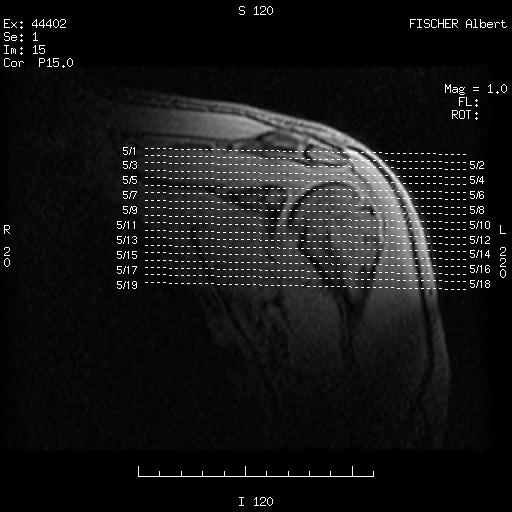

Moving from top to bottom - looking up my left arm. My head is away from you, my back towards the bottom.